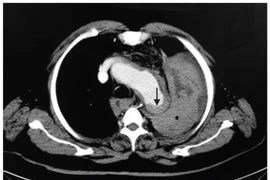

Bệnh nhân bất ngờ hôn mê sau khi hắt hơi. Bác sĩ kiểm tra qua chụp CT xác định vỡ túi phình động mạch chủ khiến người bệnh shock và tử vong ngay sau đó.